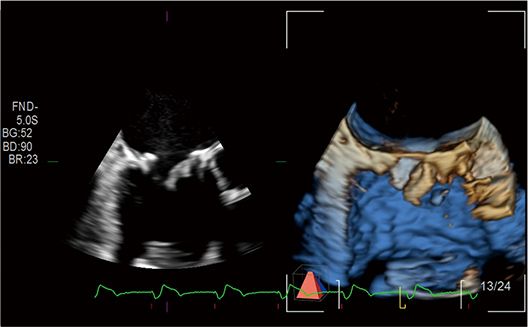

Cardiac 3D is becoming an indispensable part of the cardiac examination. Diagnostic information is attained at the next level for diagnosis and treatment in cardiac disease. The high quality product is achieved in all aspects of image quality, operability, and functionality.